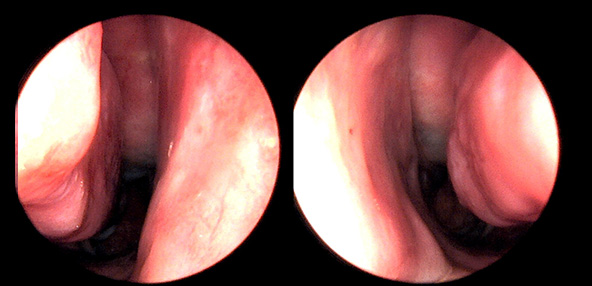

※ 비중격 비염 수술 후 생길 수 있는 부작용으로는 출혈, 감염, 염증이 있을 수 있습니다.

본 사진은 의료기관에서 진료를 본 환자이고, 전후 사진 인물이 동일인이며,동일조건에서 촬영이 되었습니다.